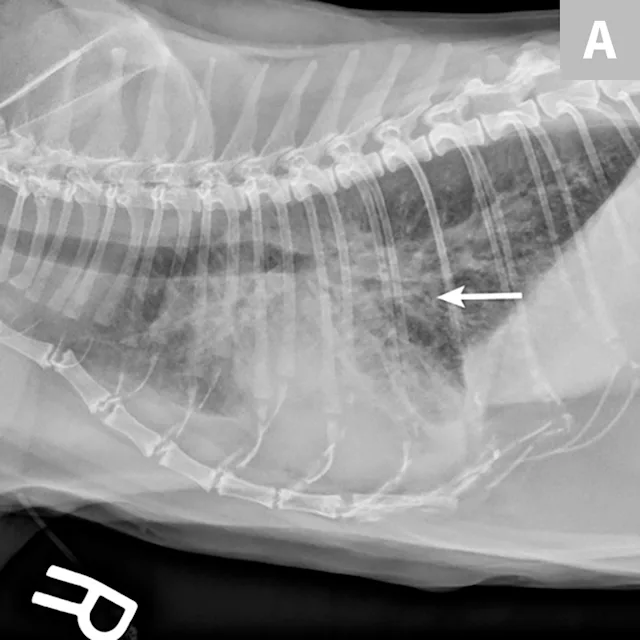

Radiographic evaluation is variable. Classic cranioventral distribution is less common in cats (Figure 3). A bronchial pattern is most common; however, bronchointerstitial, alveolar, and more structured pseudonodular patterns can occur.6,8 Occasionally, pulmonary abscesses may be appreciated and resemble pulmonary neoplasia (Figure 4).

FIGURE 4

Radiograph of pulmonary abscessation. The pulmonary nodules (arrows) could be mistaken for pulmonary neoplasia. The margins of these nodules are slightly less well demarcated than in neoplasia. Improvement was achieved with antibiotic therapy.